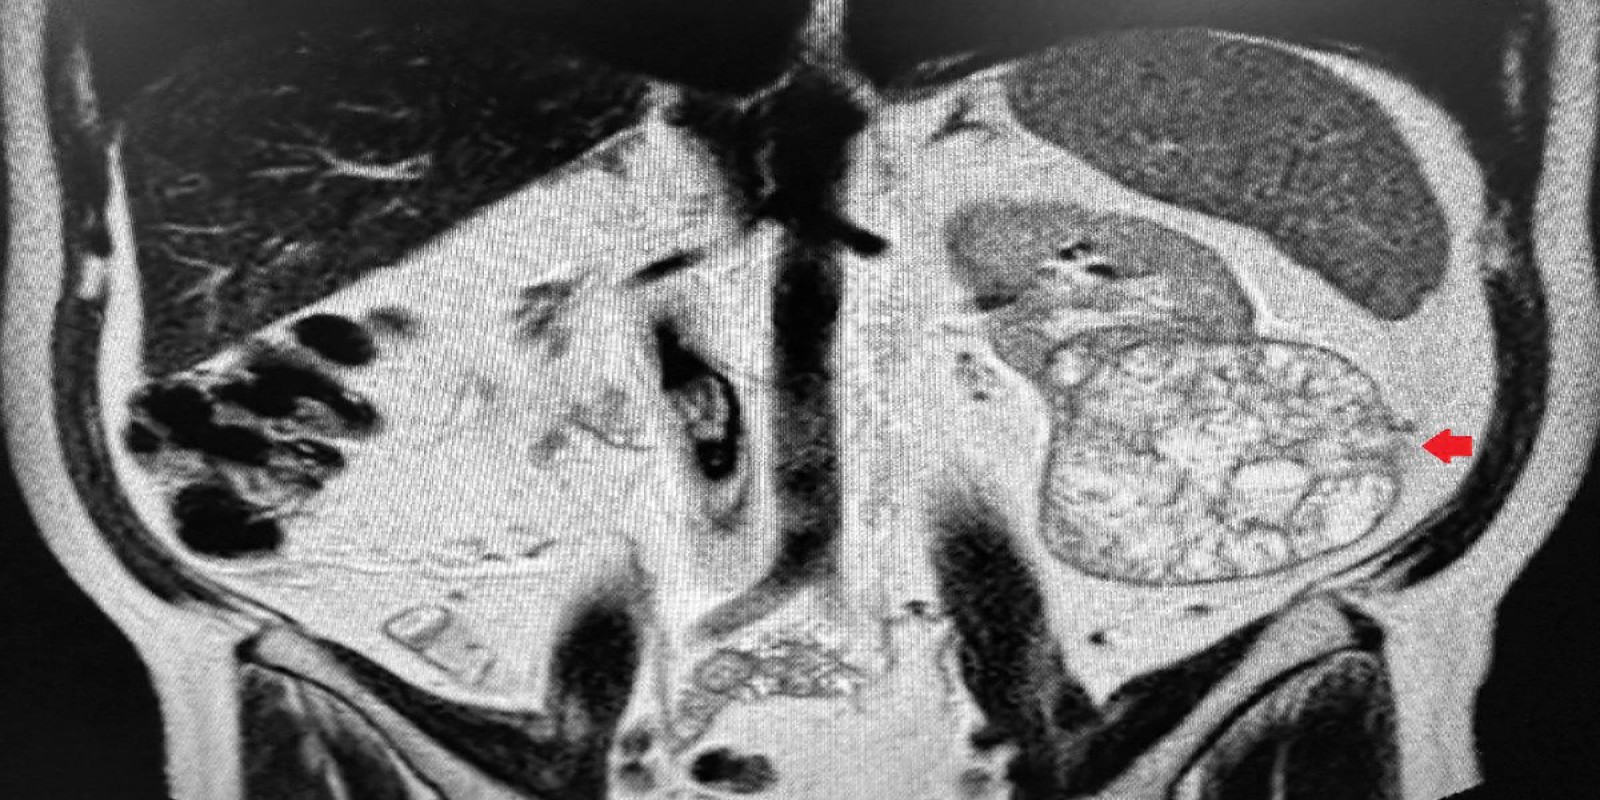

Tumor de células claras

Clear Cell Renal Carcinoma